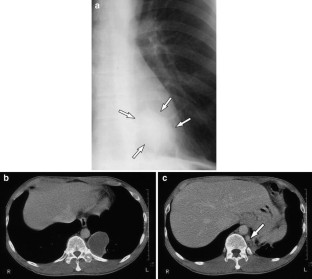

Fig. 4